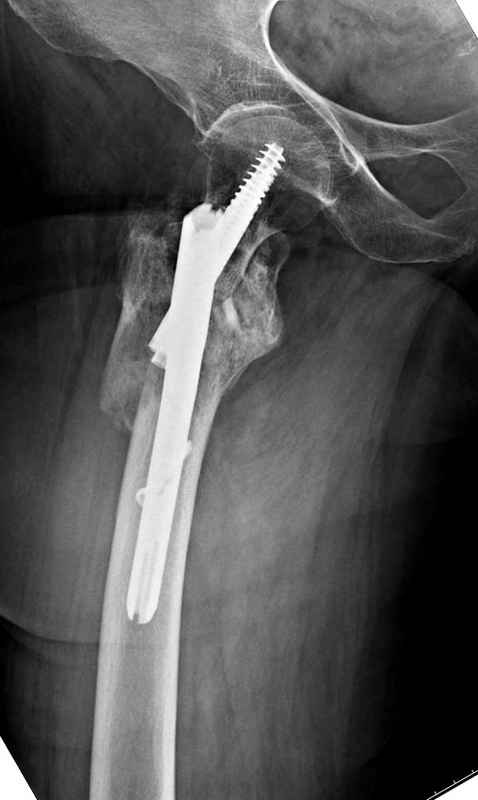

Из фиксаторов, мы бы применили цефаломедуллярные, потому что они "по закону моментов" из-за короткого рычага от центра головки к диафизу и по принципу "головка диафиз" механически лучше выдерживают нагрузки, чем пластины.

Здесь пара случаев фиксации похожих переломов:

первый высокоэнергетическая травма 36 лет

судя по картинкам с ЭОПа явно использовались приемы непрямой репозиции под его контролем, а так же интраоперационный ЭОП-контроль положения винтов, без такого контроля операция может ухудшить ситуацию (опять же учтите сроки) т.к. результат буде зависеть в большей степени от искусства хирурга, а не от технологии